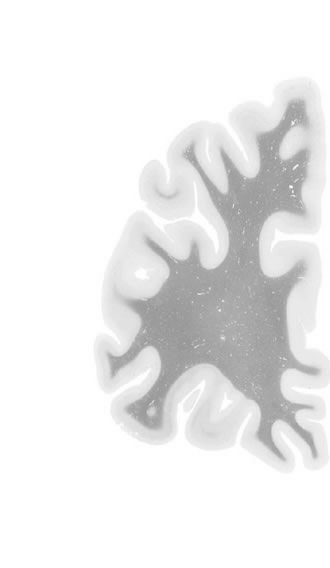

Frontal sections (Nissl) from the Atlas Brain:

Macroscopy

Slice ID:

r1-0050

Plate NR:

05

Position:

-34,5 mm